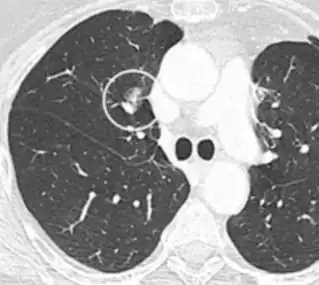

A lung nodule or pulmonary nodule is a relatively small focal density in the lung. A solitary pulmonary nodule (SPN) or coin lesion,[1] is a mass in the lung smaller than three centimeters in diameter. A pulmonary micronodule has a diameter of less than three millimetres.[2] There may also be multiple nodules.

One or more lung nodules can be an incidental finding found in up to 0.2% of chest X-rays[3] and around 1% of CT scans.[4]

The nodule most commonly represents a benign tumor such as a granuloma or hamartoma, but in around 20% of cases it represents a malignant cancer,[4] especially in older adults and smokers. Conversely, 10 to 20% of patients with lung cancer are diagnosed in this way.[4] If the patient has a history of smoking or the nodule is growing, the possibility of cancer may need to be excluded through further radiological studies and interventions, possibly including surgical resection. The prognosis depends on the underlying condition.